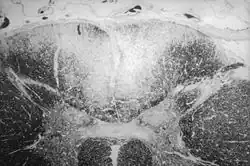

Section of human skull damaged by late stages of neurosyphilis